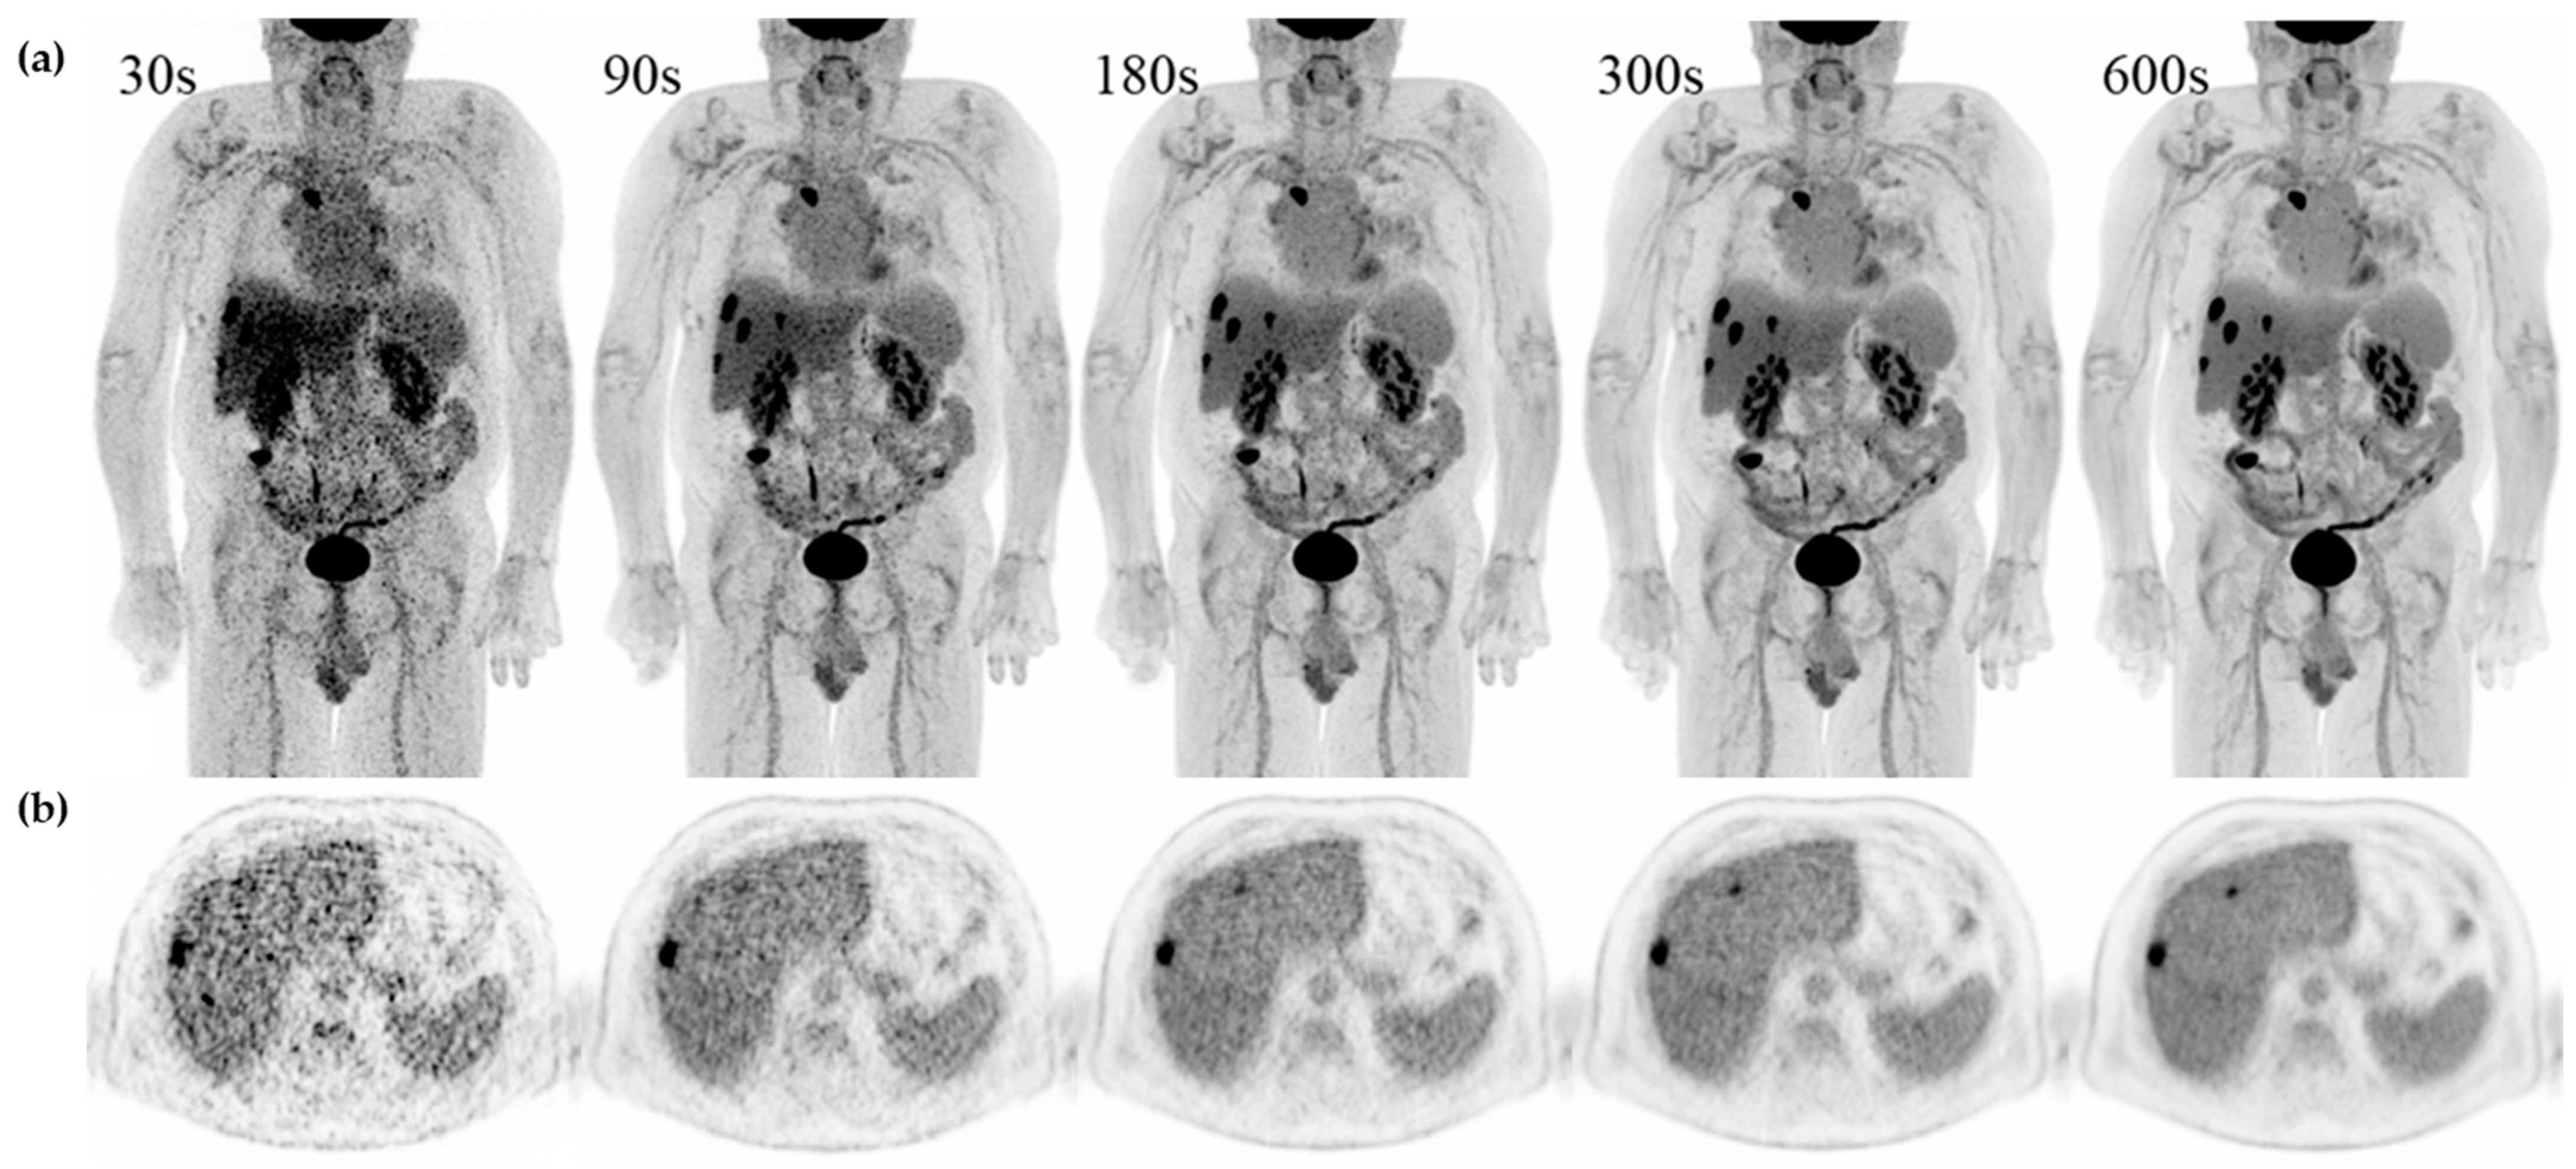

See Figure 4 for examples of a single set of scans across acquisition times.

Figure 4. Examples of a single set of scans across acquisition times in a 71 y male referred for recurrent hepatic cancer. (a) Maximum intensity projection (MIP) and (b) axial slice with simultaneous display of liver, ventricle, and spleen from 30 s, 90 s, 180 s, 300 s, and 600 s from the same patient.